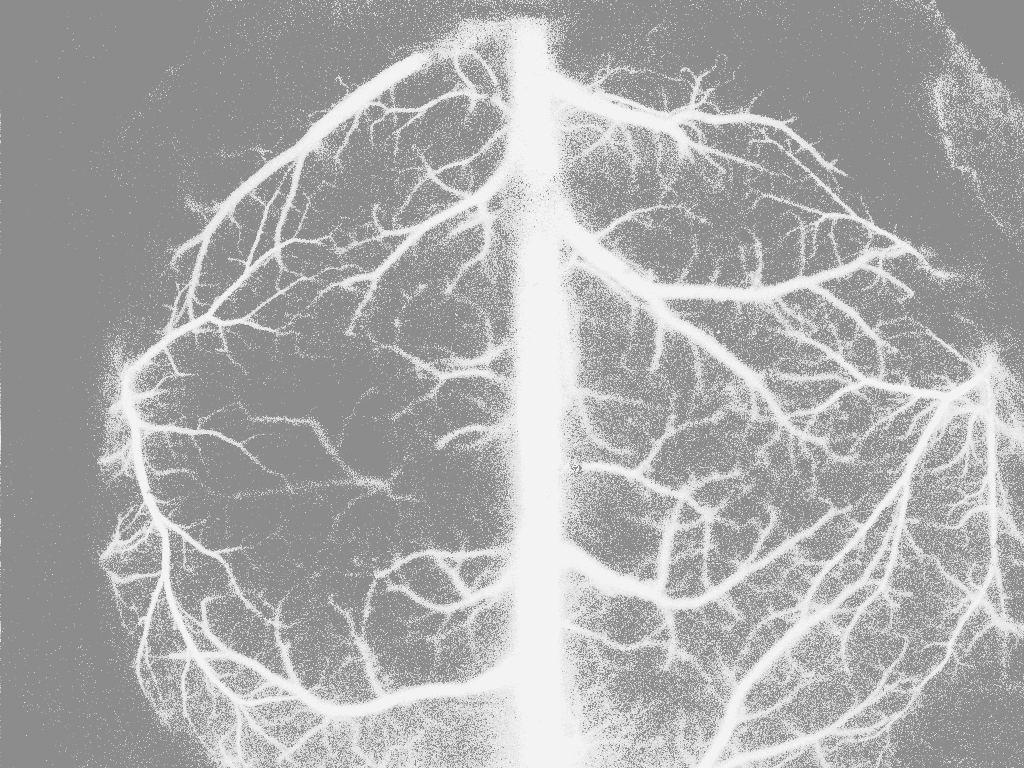

5. 上述直方图均衡算法还存在一个问题,就是当图像的0像素值占很大比例时,从起始的0像素值的累加概率就很大了,导致后面的1~255像素值的累加概率均变得很大,从而造成直方图均衡化之后的像素值都偏大。比如下图,可以看到直方图均衡化之后图像变白了,严重失真。

原图

直方图均衡化之后的图像

运行上述代码,得到结果,可以看到直方图均衡化之后,像素值不会再有整体偏高的问题。